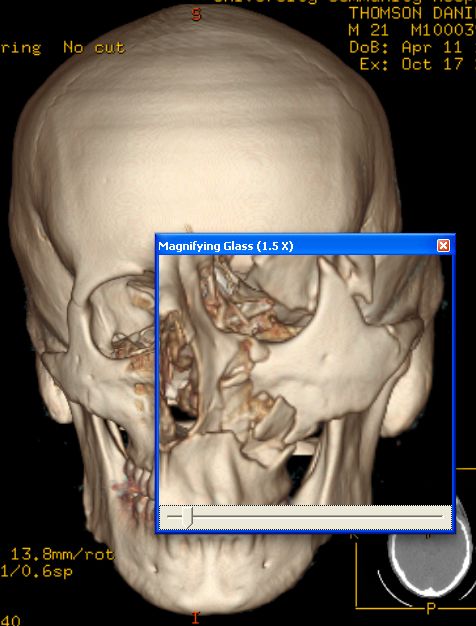

| Danny Thomson estava jogando beisebol com o irmão menor quando de repente este acertou a bola em cheio que veio, a mais de 160 por hora, em direção ao seu rosto. A bolinha acertou sua bochecha esquerda e fez um tamanho de um estrago que precisou de cirurgia para ser reparado. Vejas as imagens: |

dois olhos roxos eu não sei, mas a 4° foto eh o rabisco q os medicos fazem antes da cirurgia, pra sabe aonde eh q tem q mexe e tals...

e a quarta foto?

Não entendi a quarta foto.

Lili, nao tenho certeza, mas parece que é o desenho dos ossos do rosto dele (com caneta, é claro xD)

Oq é aquilo roxo na cara dele na 4° foto? .-.

a bola rachou o cranio dele, ou eu que vi a tomografia zuada?????

Tomografia 3D show de bola !!!!